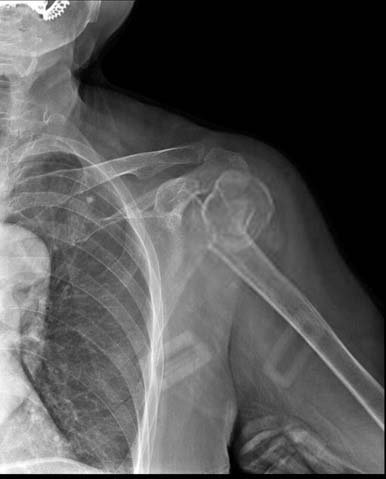

Shoulder Fracture

X-rays of the affected part will lead to the diagnosis. In some cases CT or MRI

may be required.

Proximal Humerus Fractures:

Non operative treatment can be tried if there is no/minimal displacement. If the

fragments are displaced a surgery is required either using plates and screws or a

shoulder replacement in some cases.